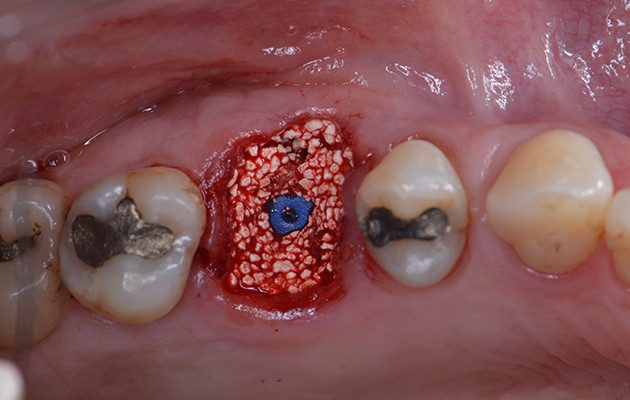

10 | Preenchimento do alvéolo fresco com biomaterial substituto ósseo de origem sintética. Destaque para o Tapa Implante colocado para prevenir a entrada do biomaterial dentro do implante

11 | Cicatrizador Multifuncional Arcsys posicionado sobre o implante.